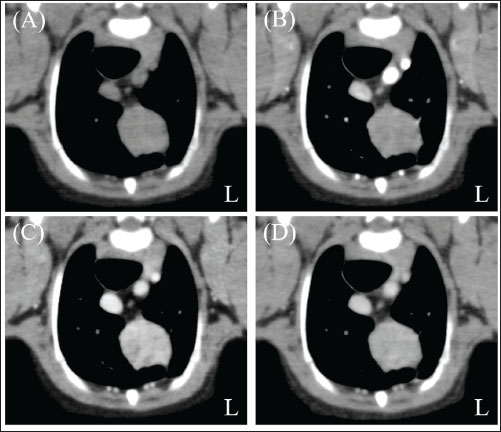

A neutered 9-year-old male Papillon weighing 3.5 kg was referred to the Okayama University of Science Veterinary Medical Teaching Hospital for examination and treatment of an incidentally discovered mass in the cranial intrathoracic cavity during regular medical checkups. The dog had no clinical signs and was in good general condition. However, a mass in the cranial thoracic region was detected by chest radiography. Blood tests showed no hypercalcemia, and arterial blood gas analysis showed no problems (Table 1). Polycythemia, slight hypernatremia, and hyperchloremia, which may be related to dehydration, were also observed. A chest X-ray revealed a mass of approximately 20 mm in the cranial intrathoracic cavity and mild expansion of the mediastinum (Fig. 1). The tumor-associated syndromes, such as megaesophagus and myasthenia gravis, were not observed. Computed tomography (CT) was performed under general anesthesia (Aquilion Lightning; Canon Medical Systems Co., Tokyo, Japan). Iopamidol (Oypalomin 300, Fuji Pharma, Japan) was used as a contrast medium (injection volume, 2.5 ml/kg [750 mgI/kg]; injection time, 15 seconds). Precontrast, arterial phase, venous phase, and equilibrium phase scans were obtained. The cranial intrathoracic mass (length, width, and height of 18.3, 16.0, and 18.6 mm, respectively) was a solitary lesion within the cranial mediastinum (Fig. 2). The mass was well demarcated, and there was no evidence of invasion into the surrounding blood vessels. The CT values of the mass were 43.2, 50.6, 113.1, and 102.2 HU for the precontrast, arterial, venous, and equilibrium phases, respectively (Fig. 2). These contrast enhancement effects were a preliminary diagnosis that the mass was a thymoma (Von Stade et al., 2019). Enlarged surrounding lymph nodes or distant metastasis were not detected. Due to the small size of the mass and its absence from the thoracic cavity margin, preoperative pathological examination could not be performed. Based on the CT results, the mass was provisionally diagnosed as a thymoma. The thymoma volume was measured from the length, width, and height by computed tomography using the elliptical volume formula. The cranial intrathoracic volume was measured using a 3D image analysis software (Ahmics-VAZE, PetCommunications Co., Ltd., Osaka, Japan). The cranial intrathoracic region between the first and fourth sternum at the beginning of the cranial intrathoracic cavity was assumed to be the surgical space for VATS-T (Fig. 3). The dorsal cephalic end was designated as the point where the first sternum extends perpendicularly and joins the thoracic vertebrae, and the dorsal caudal end was designated as the point where the fourth sternum extends perpendicularly and joins the thoracic vertebrae. This region was extracted and its volume was measured using the 3D volume rendering function by Ahmics-VAZE. The ratio of thymoma volume to cranial intrathoracic volume (T/CI ratio) was calculated as follows: thymoma volume/cranial intrathoracic volume × 100). The thymoma volume was 2.3 cm3, the cranial intrathoracic volume was 97.7 cm3, and the T/CI ratio was 2.4%. The thymoma volume was calculated using the approach in a previous report of two cases that described the thoracoscopic resection of thymomas (Mayhew and Friedberg, 2008). We also calculated the cranial intrathoracic volume for the dog, as it was of the same breed and weight as the two reported cases. Subsequently, we calculated the T/CI ratio. In previous reports, the thymoma volumes were 9.5 cm3 and 36.6 cm3, respectively, and the cranial intrathoracic volume was 892.8 cm3. The T/CI ratios were 1.1% and 4.1%, respectively.

Fig. 3. CT imaging of the cranial intrathoracic cavity. (A) Sagittal section. (B) Transverse section of the first sternum. (C) Transverse section of the fourth sternum. The surgical space for VATS was assumed to be the cranial intrathoracic cavity between the first and fourth sternum (A; red and yellow dotted line, respectively). Cross-sections (B and C) of the two dotted lines. The circular areas enclosed by dotted lines within the cross-sections were continuously extracted and designated as the intracranial thoracic cavity, and their volumes were measured. (L): Left side, (Cr): Cranial, (Ca): Caudal.

In recent years, VATS-T has been performed in veterinary medicine (Mayhew and Friedberg, 2008; Alwen et al., 2015; MacIver et al., 2017; Carroll et al., 2024). However, the criteria for its application have not yet been established. Two previous reports evaluated the indications for VATS-T. The first report established the following criteria: dogs weighing >20 kg, non-invasive tumors with a tumor volume of less than 300 cm³, and a tumor diameter of 8 cm (MacIver et al., 2017). The first criteria are only applicable to large-breed dogs and cannot be applied to small-breed dogs, such as those in our case. In large breed dogs, relatively small thymomas may allow sufficient thoracic cavity space for VATS-T (Mayhew and Friedberg, 2008; Alwen et al., 2015; MacIver et al., 2017; Carroll et al., 2024). However, small thymomas may not have sufficient space in the cranial intrathoracic cavity in small-breed dogs. Another report established the criterion of tumors with a maximum diameter-to-body weight ratio of approximately 0.02 (Carroll et al., 2024). The second criterion is based solely on the maximum tumor diameter and does not account for the 3D tumor volume. Additionally, the chest shape can vary significantly depending on the breed, even in dogs of the same weight. Therefore, body weight-based evaluation may not be appropriate. The feasibility of VATS-T in small-breed dogs ultimately depends on the judgment of the surgeon. In this study, the T/CI ratio obtained from CT data may provide an objective means of evaluating the relationship between thymomas and the CI in individual cases. Thymoma resection via VATS-T is feasible in small breeds of dogs. The T/CI ratio for this case (2.4%) was similar to those for previous VATS-T cases (1.1% and 4.1%, respectively). VATS-T may be feasible for cases with a T/CI ratio of approximately 5% or less.

Cranial intrathoracic cavity opened during thymectomy has no specific definition. In this study, we defined the cranial intrathoracic region using the T/CI ratio to represent the area from the tip of the first sternum to the caudal end of the fourth sternum. The tip of the first sternum is located in the cervicothoracic part and is not included in the surgical space. The actual intrathoracic cavity begins around the first sternum’s center. However, the region designated as “around the center” of the first sternum may be ambiguous when measuring the cranial intrathoracic volume. Therefore, the tip of the first sternum was designated as the cranial end. The caudal end of the fourth sternum was assumed to be the most caudal point where the actual VATS space could be used.